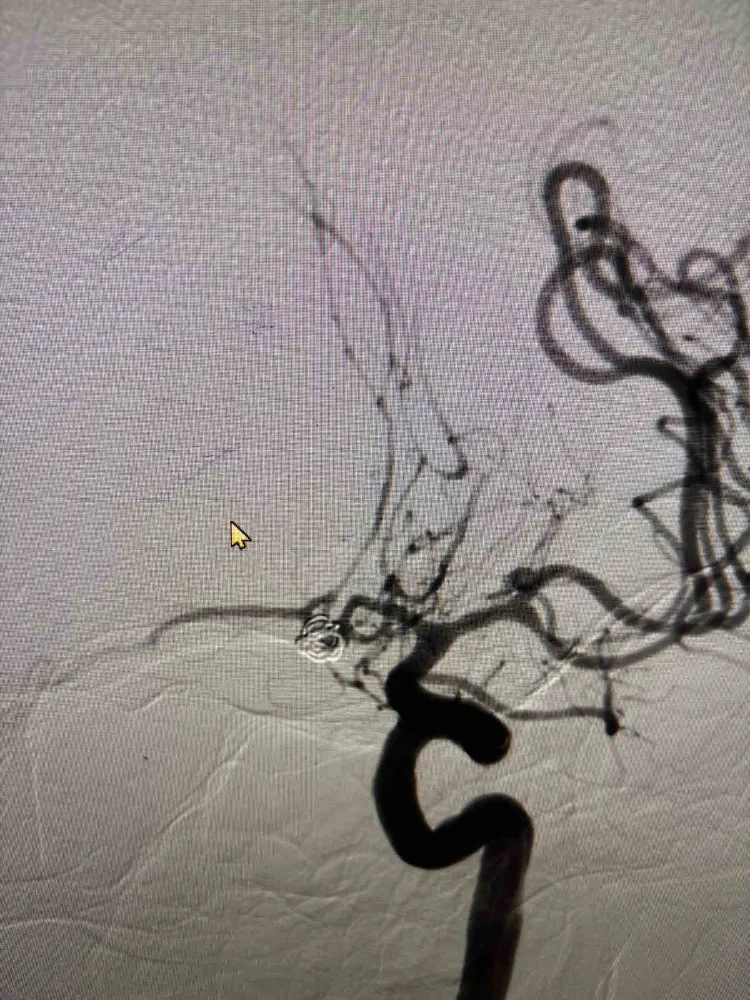

Beyin kanamaları hakkında bilgi veren Prof. Dr. Emrah Aytaç, "Beyin kanamaları tüm inmelerin yüzde 20’lik kısmını oluşturur" dedi. Fırat Üniversitesi Hastanesi Nöroloji Anabilim Dalı Öğretim Üyesi Prof. Dr. Emrah Aytaç, beyin kanamaları hakkında bilgiler verdi. Prof. Dr. Emrah Aytaç, "Hemorajik inme, yani beyin kanamaları beyni besleyen damarların ani yırtılması sonucu ortaya çıkan kalıcı nörolojik fonksiyon bozukluğudur. İki tür beyin kanaması vardır. Daha çok hipertansiyon sonrası görülen beyin parankiminin içerisinde olan kanamalar ve beyin baloncuklarının patlaması sonucu oluşan kanamalar şeklindedir. Beyin kanamaları tüm inmelerin yüzde 20’lik kısmını oluşturur. Bunun yaklaşık yüzde 15’lik kısmının parankimal intraserebral hemoroji (yani beyin dokusu içinde olan kanama) beyin kanamaları oluşturur. Yaklaşık yüzde 5’lik kısmını ise subaraknoid (yani beyin zarları arasına olan kanama) kanamalar oluşturuyor. Beyin baloncuğu sonrasında ortaya çıkan beyin kanamalarında hastaların dikkatli olması gerekiyor. Bu beyin kanamalarında şiddetli baş ağrısı ile başlıyor. Hastanın hayatında daha önce hiç hissetmediği kadar şiddetli baş ağrısı hisseder. Bunun yanında, bulantı, kusma ve bilinç bozukluğu oluşur. Baloncuğa bağlı olarak gelişen beyin kanamalarında bazen kanama olmadan bir ay öncesine kadar dayanan öncül baş ağrıları ile hastalar bize başvurur. Bu açıdan dikkatli olunmalıdır" diye konuştu.  Aytaç, "Beyin baloncukları kanaması durumunda bu hastaların yüzde 10’luk kısmı kanama olur olmaz hayatlarını kaybeder. Geriye kalan yüzde 50’lik kısmı da bir ay içerisinde hayatlarını kaybeder. Çok ölümcül seyreden bir hastalıktır. Kanayan veya kanamayan beyin baloncuğu tespit edildiğinde o baloncuğun kapatılması ya da cerrahi işlem ile klipsleme denilen işlem ile baloncuğun ortadan kaldırılması gerekir. Diğer bir tedavinin ise kasıktan girilerek baloncuğun tespit edilerek metal örgüler ile baloncuğun kapatılması işlemidir. Bu yöntem, hastalarda hayat kurtarıcı bir işlemdir. Yeni başlayan baş ağrısı, bilinç bulanıklığı ve ateş gibi belirtileri olan hastaların, hiç vakit kaybetmeden acil servislere başvurmaları gerekmektedir" şeklinde konuştu.